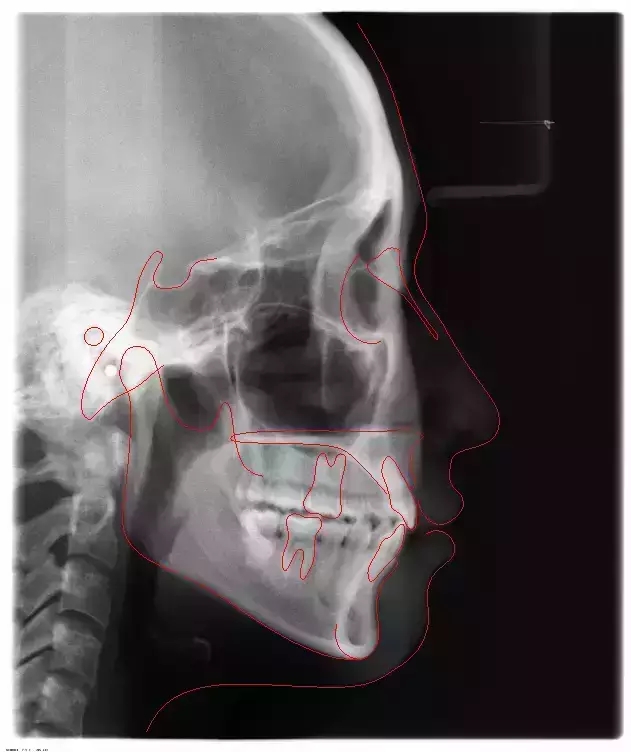

Damon 病例分享:安氏 II 類(lèi)二分類(lèi)露齦笑的矯治(董一磊)

患者信息